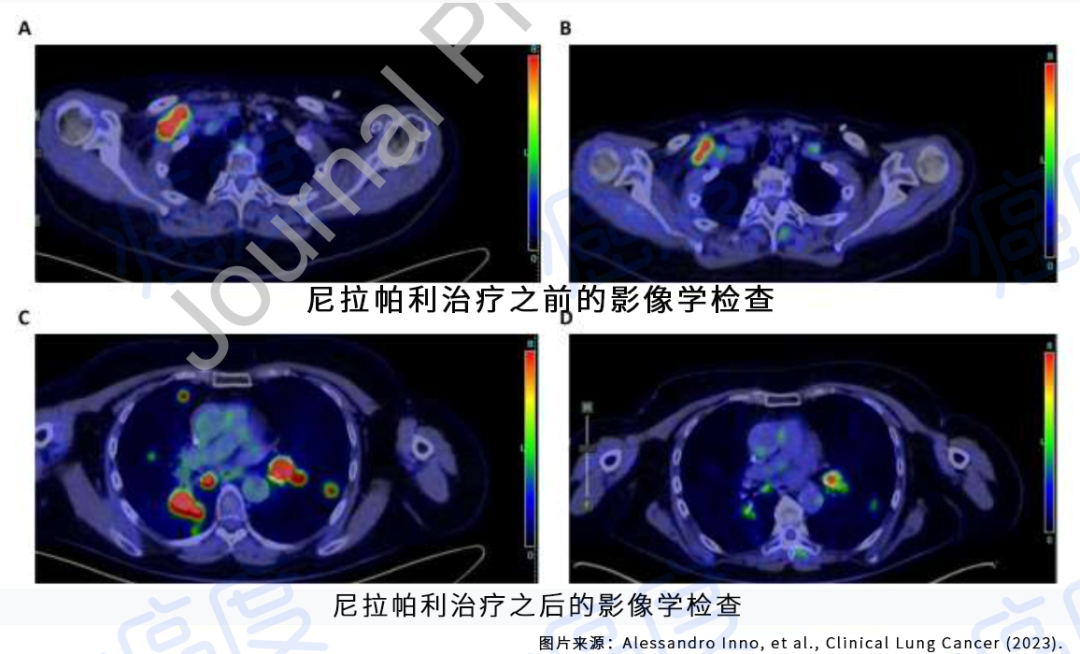

何医生介绍,三代EGFR-TKI伏美替尼由于化学结构上的优化,具备提高药物浓度而不增加副反应的可能,国内外有相似的研究报道。因此,建议李先生开始口服“双倍剂量伏美替尼”靶向治疗。令人欣喜的是,1个月后复查,李先生肺部及肝脏转移灶较前明显退缩,疗效评价达到部分缓解。

双肺粟粒样转移和肝脏转移明显缩小

目前,李先生仍在口服“双倍剂量伏美替尼”治疗,肿瘤控制良好,已经维持稳定近一年,且并未有副作用,目前患者生活质量良好。